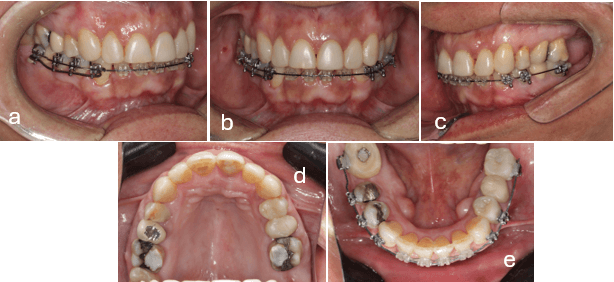

Se inicia el tratamiento con cementación superior, con Brackets Elation MB(GAC Orthomax, Dentsply Sirona orthodontics, Nueva California, USA) de prescripción Roth de slot 0.022”, arco inicial 0.014 Termocooper (Orthometric, Marilia, Sao Paulo, Brasil) (fig. 4a y b).

Se procede a realizar la cementación de botones simple de ortodoncia (Morelli, Sorocaba, Sao Paulo, Brasil) en la pieza 1.6 solo en la cara palatina y en 2.6 se colocan en la cara vestibular y palatina (fig. 4c y 4d).

Se instalan de 2 mini-implantes interradiculares en la hemiarcada izquierda 8x2x1.5 Morelli, (Sorocaba, Sao Paulo, Brasil) (fig. 4d). El primero es ubicado en la zona del vestíbulo, entre la raíz mesial segundo molar maxilar izquierdo y la raíz distal del primer molar superior izquierdo. El segundo en la zona palatina, entre la raíz palatina del segundo premolar superior izquierdo y la raíz palatina del primer molar superior izquierdo.

Son instalados 2 mini implantes 8x2x1.5 Morelli (Sorocaba, Sao Paulo, Brasil) en la hermiarcada superior derecha de igual forma a lo anteriormente descrito. (fig.4d) Esto considerando el volumen de la mucosa palatina, vestibular, del hueso y de la cortical. Fue implementada una fuerza de intrusión de 40 gramos por cada raíz.

Fue realizada la exodoncia de la pieza 4.6 por tener corona defectuosa, posteriormente se instala la aparatología inferior con Brackets Elation MB (GAC Orthomax, Dentsply Sirona orthodontics, Nueva California, USA) de prescripción Roth de slot 0.022. Arco inicial 0.014 Termocooper Orthometric (Marilia, Sao Paolo, Brasil) (fig.5e)

Se instala mini-implante interradicular de 8x2x1.5 Morelli (Sorocaba, Sao Paolo, Brasil) en la región retromolar del cuarto cuadrante. Se inicia con mecánica de distalización de dicho cuadrante aplicando 250 gramos de fuerza. Se continua en el maxilar superior con alineación y nivelación y activación de mecánicas de intrusión de primeros molares superiores (1.6 y 2.6). (fig.5d).

Figura 4.- Cementación superior y biomecánicas de intrusión

a) Lateral derecha b) Frontal c) Lateral izquierda d) Oclusal superior e) Oclusal inferior

Figura 5.- Cementación inferior, biomecánicas de intrusión de molares superiores y distalización del cuarto cuadrante inferior.